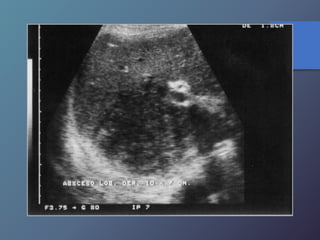

Abscesos Hepáticos Parasitarios

La infección hepática por entamoeba histolytica

es la manifestación más frecuente de amibiasis

extraintestinal

• Alrededor del 15% de los pacientes presentan diarrea

en el momento del DX.

• Son redondas u ovales.

• Ausencia de pared, hipoecogenicos en relación al

hígado.

• Ecos internos de nivel bajo, finos y continuidad con el

diafragma.

• Ubicados a nivel del lóbulo derecho

Abscesos Hepáticos Parasitarios Lainfección hepática por entamoeba histolytica es la manifestación más frecuente de amibiasis extraintestinal • Alrededor del 15% de los pacientes presentan diarrea en el momento del DX. • Son redondas u ovales. • Ausencia de pared, hipoecogenicos en relación al hígado. • Ecos internos de nivel bajo, finos y continuidad con el diafragma. • Ubicados a nivel del lóbulo derecho